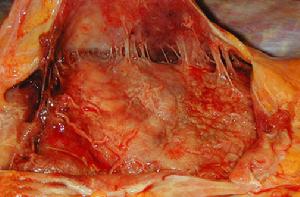

心包炎炎症反應的範圍和特徵隨病因而異。可為局限性或瀰漫性,病理變化有纖維蛋白性(乾性)和滲出性(濕性)兩種,前者可發展成後者。滲液可為漿液纖維蛋白性、漿液血性、出血性或化膿性。炎症開始時,壁層和髒層心包出現纖維蛋白、白細胞和內皮細胞組成的滲出物。以後滲出物中的液體增加,則成為漿液纖維蛋白性滲液,量可達2~3L,外觀呈草黃色,清晰,或由於含有較多的白細胞及內皮細胞而混濁;如含有較多的紅細胞即成漿液血性。滲液多在2~3周內吸收。結核性心包炎常產生大量的漿液纖維蛋白性或漿液血性滲出液,滲液存在時間可長達數月,偶呈局限性積聚。化膿性心包炎的滲液含有大量中性粒細胞,呈稠厚的膿液。膽固醇性心包炎滲液中含有大量的膽固醇,呈金黃色。乳糜性心包炎的滲液則呈牛奶樣。